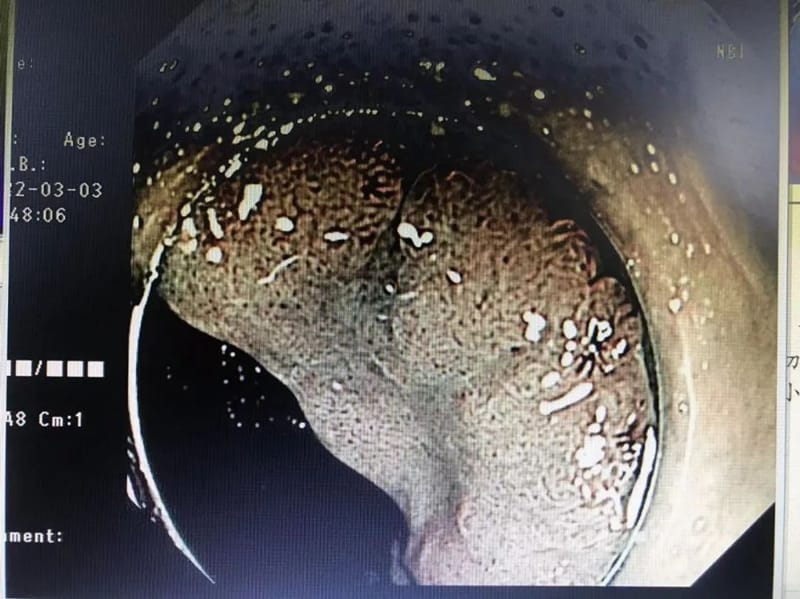

89岁高龄的男性患者张某,因外院结肠镜检查发现一枚大小约1.8*1.5cm的直肠侧向发育型肿瘤入院,原本这么高龄的患者,常规采用保守治疗,经郭军主任查看病人,考虑其直肠侧向发育型肿瘤为早期病变,全麻插管下内镜下微创切除无疑是最好的选择,且老人身体健康,无基础性疾病,手术指征良好,在充分的讨论后,建议内镜下微创切除。在经得患者及家属同意后,消化内科团队与麻醉与围术期医学科医师密切配合,成功为患者实施了经内镜直肠病灶粘膜剥离术,病灶完整切除,手术顺利,术后患者恢复良好。